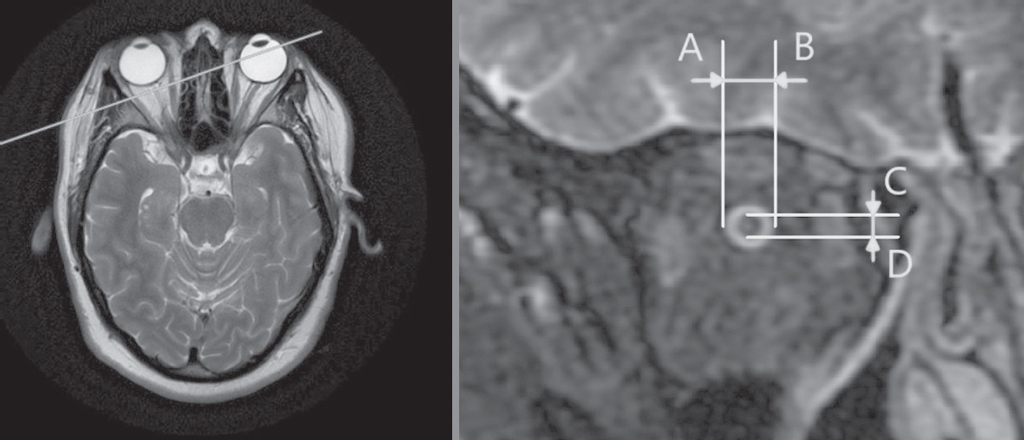

To assess the SAS width, we used a snapshot of the transverse section of the ON made 3 mm behind the eyeball using a GE Optima MR450w magnetic resonance tomograph (GE, USA) with a magnetic field induction of 1.5 T (Figure 3). The study was performed using a head coil where the patient’s head was immobilized with special cushions. The patients fixed their gaze on their own through a mark applied to a magnetic coil, which enabled to reduce eye mobility and obtain more contrasting images. Before the study of the ON, a standard protocol for scanning the structures of the brain in the axial and sagittal planes was performed, without an inter-slice interval. Standard scan images were required for the correct positioning and direction of the ON slices. A targeted study of ON was performed in the oblique coronal plane in the fat suppression mode. On the obtained images of the cross section of the ON, the width of the SAS was determined as half the difference between the average diameter of the MR image of the ON slice with its sheath (A–B) and the average diameter of the MR image of the ON slice without its sheath (C–D). Measurements were performed using the RadiAnt Dicom Viewer software for X-ray images.

Fig. 3. Cross-sectional image of the optic nerve (right) taken 3 mm behind the eye using MRI. A–B – is the diameter of the optic nerve with its sheaths; C–D – is the diameter of the optic nerve without its sheaths

Рис. 3. Изображение поперечного среза зрительного нерва (справа), выполненного в 3 мм за глазным яблоком, с помощью магнитно-резонансного томографа. A–B — диаметр зрительного нерва с оболочками; C–D — диаметр зрительного нерва без его оболочек